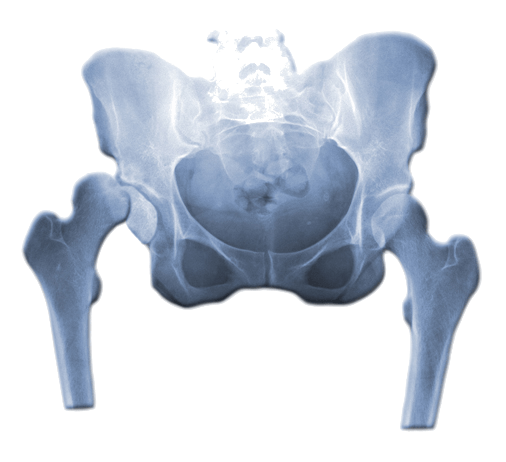

Zwapnienia (kalcyfikacje) to schorzenie charakteryzujące się odkładaniem soli wapnia w tkankach miękkich, takich jak ścięgna, więzadła, mięśnie czy kaletki maziowe. To zjawisko może prowadzić do stanu zapalnego, ograniczenia ruchomości oraz bólu. W ortopedii zwapnienia są szczególnie częste w okolicy stawu barkowego, łokciowego, biodrowego oraz w ścięgnach Achillesa. Przyczyny tego zjawiska mogą być złożone, a leczenie zależy od wielu czynników, takich jak lokalizacja i rozmiar zwapnień oraz objawy, które powodują.

Zwapnienia są wynikiem nieprawidłowego odkładania się soli wapnia w tkankach, które normalnie nie powinny zawierać tego pierwiastka. Zjawisko to jest najczęściej spotykane w obrębie ścięgien, takich jak ścięgno nadgrzebieniowe w barku (ścięgno rotatorów), a także w więzadłach i kaletkach. Właściwa tkanka miękka nie powinna być zwapniała, dlatego obecność depozytów wapnia może powodować znaczne dolegliwości.